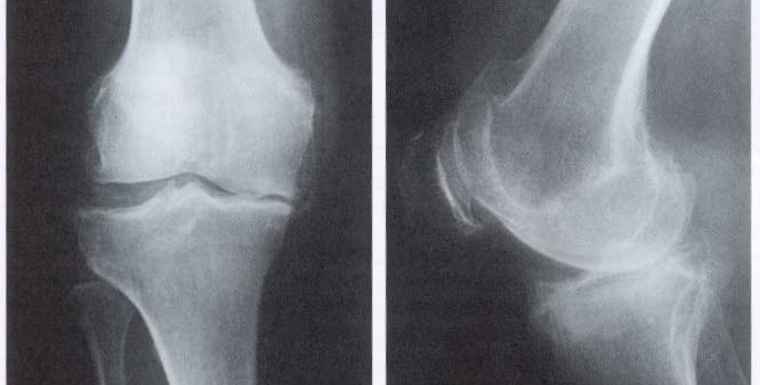

Остеоартрит фасеточных суставов: медицинские снимки и схемы